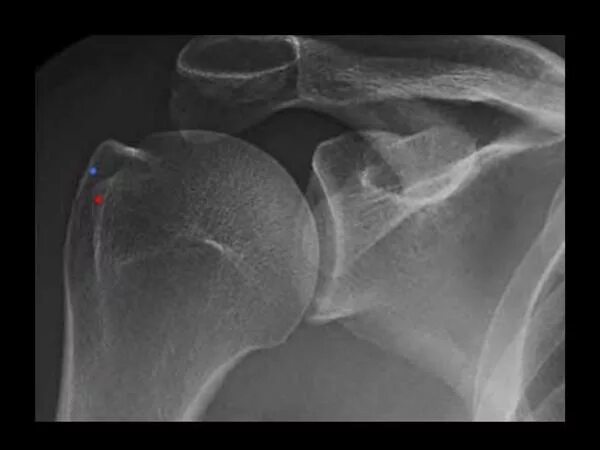

Перелом большого бугорка реабилитация